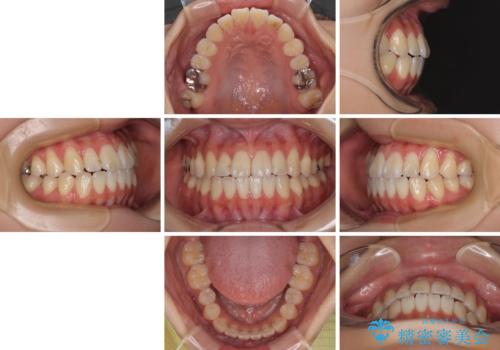

舌の突出癖が原因 インビザライン矯正による開咬改善

- 患者様

- 20代女性

- 矯正装置

- インビザライン

- 前歯の開咬を気にして来院された患者様です。

開咬の治療は、前歯を閉じるように動かすとともに、上下臼歯を圧下(骨内にめり込ませる)させることで進めて行きます。

インビザラインは臼歯の圧下を効果的に行えるため、インビザラインを用いて矯正治療を行うこととしました。

オープンバイトは舌の突出癖により誘発され、治療後も突出癖が残っている容易に後戻りしてしまいます。

治療期間を短縮するためにも、舌突出癖の改善が極めて重要となります。

特にインビザラインではIPRという歯と歯の間を削る処置を多用するため、後戻りによりスペースが生じやすくなるため、治療初期段階での舌のトレーニングが必須となります。